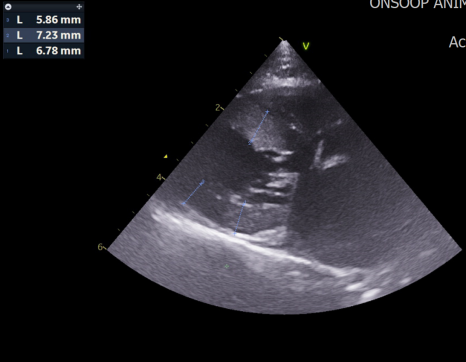

심장초음파 검사 결과 / 출처: 24시온숲동물의료센터

심장 초음파 검사: HCM(비대성 심근병증) 과 SAM(승모판연관 이첨판전방이동) 소견이 확인되었습니다.